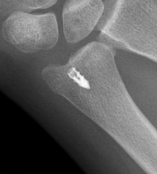

Options

| K wire stabilization | ORIF ulna styloid fracture | Repair TFCC |

2 x 1.6 mm K wires Proximal to sigmoid notch Ulna to radius Ensure K wire exits radius in case of breakage |

| AO surgery K wire fixation DRUJ |